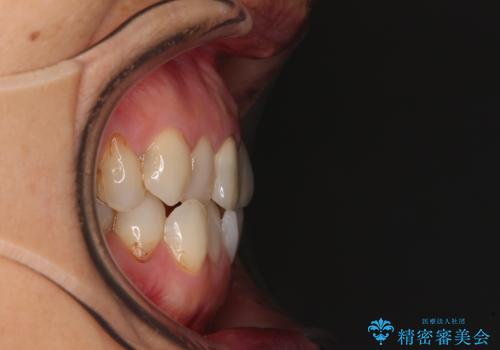

デコボコと銀歯 矯正治療とセラミック治療で綺麗な口元に

- 前歯のデコボコと口を開けたときに見える銀歯を気にして来院された患者様です。

矯正治療後に銀歯をセラミッククラウンなどに置き換えていくと、どうしても後戻りを起こしてしまうため、矯正治療が概ね終了した時点で銀歯を全てセラミックとし、最後に仕上げでインビザラインにを用いて細かいデコボコを改善していくこととしました。

とても明るい口元となり、人目を気にせず、大きく口を開けて笑えるようになりました。